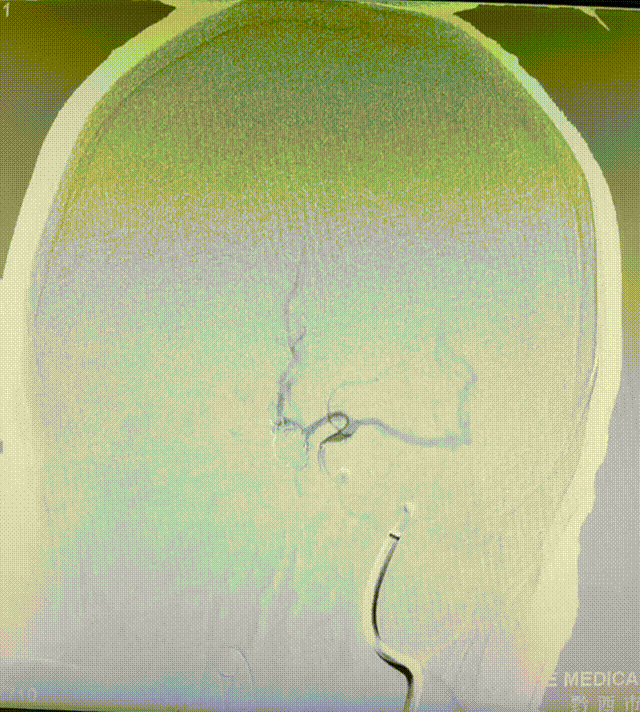

CTA:见前交通动脉瘤,大脑前动脉共干,动脉瘤16*10*9大小,双侧A2均由动脉瘤上发出,右侧A2开口呈180°回旋。

术前造影显示大脑前动脉瘤。